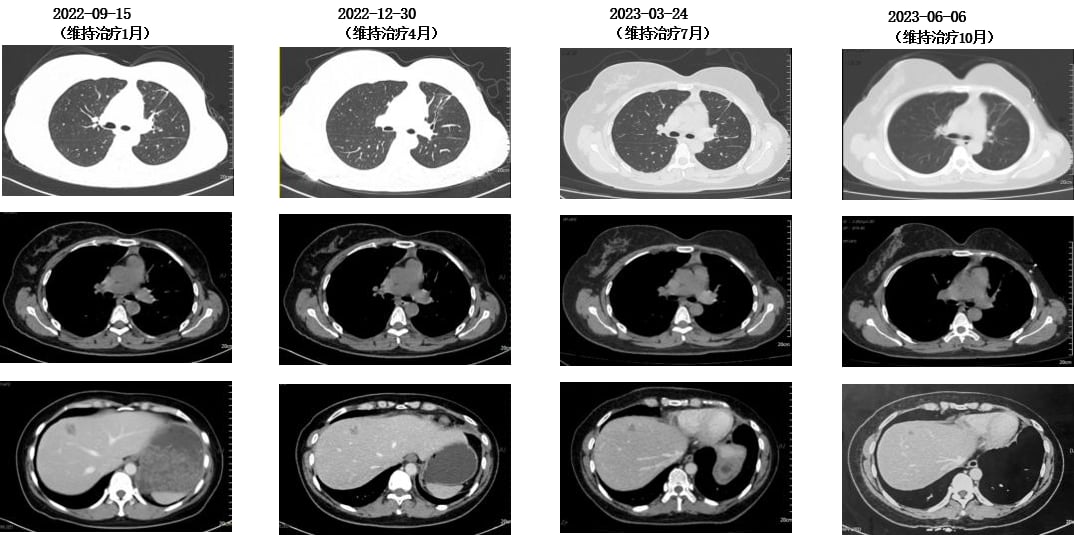

- 靶向联合化疗:TCbH方案(曲妥珠单抗+白蛋白结合型紫杉醇+卡铂)4周期,随后TH方案(曲妥珠单抗+白蛋白结合型紫杉醇)2周期。

- 骨转移治疗:定期静脉注射唑来膦酸,并口服碳酸钙D3片和骨化三醇进行补钙。

令人惊喜的是,治疗后患者疗效评价为部分缓解(PR),特别是颅内病灶达到了完全缓解(CR),且长期无症状。这充分证明了HER2靶向治疗的强大效果,即使是脑转移这种棘手的情况,全身治疗也能取得显著成效。随后,患者进入维持治疗阶段,使用氟维司群+曲妥珠单抗+戈舍瑞林,病情持续稳定。